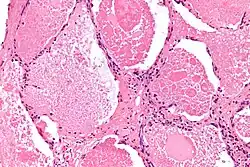

Micrograph of pulmonary alveolar proteinosis, showing the characteristic airspace filling with focally dense globs referred to as chatter or dense bodies. H&E stain. | |

Lung washings or tissue for histopathologic analysis are most commonly obtained using bronchoalveolar lavage and/or lung biopsy.[13] Characteristic biopsy findings show filling of the alveoli (and sometimes terminal bronchioles) with an amorphous eosinophilic material, which stains strongly positive on PAS stain and the PAS diastase stain. The surrounding alveoli and pulmonary interstitium remain relatively normal.[14] Electron microscopy of the sample, although not typically performed due to impracticality, shows lamellated bodies representing surfactant.[15] An alternative diagnosis with similar histomorphologic findings is Pneumocystis jirovecii pneumonia.[15]

Lung washings characteristically yield a fluid which is "milky"composition. Under the microscope, samples show 20-50 micrometer PAS-positive globules on a background of finely granular or amorphous PAS-positive material. There is typically a low numbers of macrophages and inflammatory cells (although this is variable).[14][15]